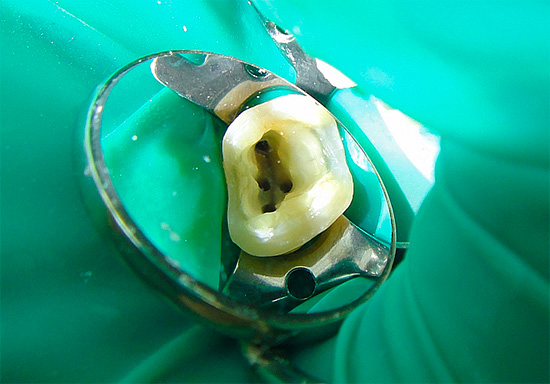

Foto dei residui di polpa rimossi dal canale radicolare del dente:

Per gli stessi motivi, è impossibile eseguire l'amputazione vitale preservando solo la polpa della radice, poiché è quasi sempre già coinvolta nei processi di necrosi.